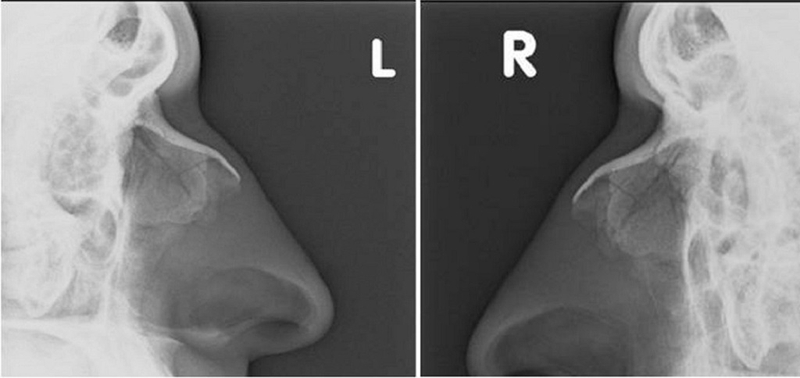

Trong trạng thái bình thường, hình ảnh của các hốc xoang sàng trước và sau sẽ hiển thị đều màu sáng và các vách ngăn giữa các tế bào sẽ được phác thảo rõ ràng.

Khi các hốc xoang bị ảnh hưởng bởi bệnh lý, hình ảnh sẽ cho thấy các tế bào trong các hốc xoang trở nên mờ đục hoặc đặc do sự tích tụ của dịch mủ hoặc niêm mạc dày, cũng như sự xuất hiện của polyp. Nếu các vách ngăn giữa các hốc xoang trở nên mờ đi hoặc bị phá hủy, điều này có thể cho thấy nguy cơ của việc xuất hiện polyp mũi hoặc u ác tính.